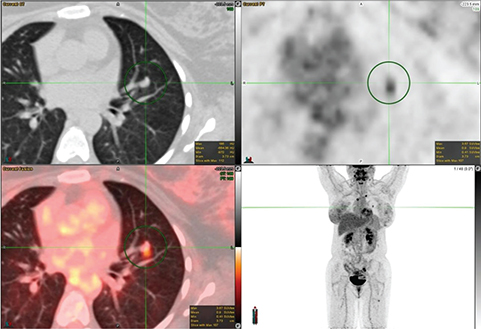

Staging

Accurate staging of lung cancer is mandatory after the diagnosis for appropriate patient management. Many guidelines such as the National Comprehensive Cancer Network (NCCN), the ESMO Clinical Practice Guidelines, the American College of Radiology Appropriateness Criteria, the guidelines of the Society of Nuclear Medicine and Molecular Imaging, and the guidelines of the American College of Chest Physicians recommend 18F-FDG PET/CT for evaluation of patients with stage I to stage IV NSCLC (2124). For the staging of NSCLC, the most standardized and recognized system is the TNM system, where T denotes the size of the primary tumor, its location and level of invasion; N indicates the status of regional lymph nodes; and M refers to the presence or absence of more distal metastases (25). FDG PET/CT plays a vital role in the staging of T, N, and M of lung cancer and an example of FDG avid primary and metastatic tumors is shown in Figure 4.

Fig 4

Figure 4. Right upper lobe lung mass that was pathologically confirmed as poorly differentiated non-small cell lung cancer. FDG PET/CT images include axial CT (top left panel), axial PET (top right panel), fused axial PET/CT (bottom left panel), and maximum intensity projection (MIP) PET image (bottom right panel). In the green circle, there is a spiculated pleural based right upper lobe mass with surrounding interlobular septal thickening on CT with intense FDG uptake on PET. There are additional FDG-avid metastatic foci within the lungs and mediastinal lymph nodes.